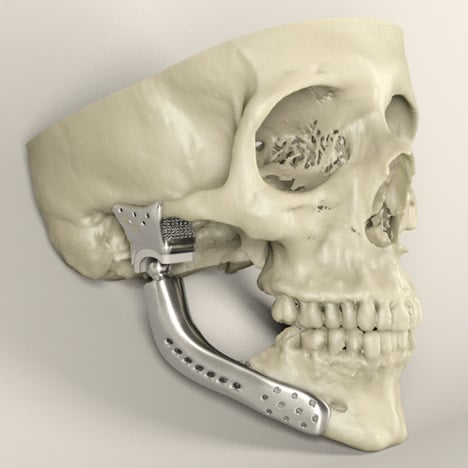

Metal has good toughness, fatigue resistance, and ductility, making it the most widely used type of biomedical materials. It’s mainly used for the treatment of tissues and organs such as bones, teeth and blood vessels.

At present, the metal materials used for biomedical 3D printing mainly include titanium alloys, cobalt-chromium alloys, stainless steels, and aluminum alloys. Medical researchers have used titanium alloy to print artificial bones and successfully implant them in human bodies. However, the disadvantage of this technology is that the metal materials suitable for 3D printing are too expensive for patients to bear.

Although metals have been widely used in the medical field due to their good characteristics, they are also subject to corrosion and abrasion after implantation, resulting in poor overall performance and inflammatory body reactions. And matching degree between metal material implants and living organisms is the current problem that needs to be solved in 3D printing medical metal materials.